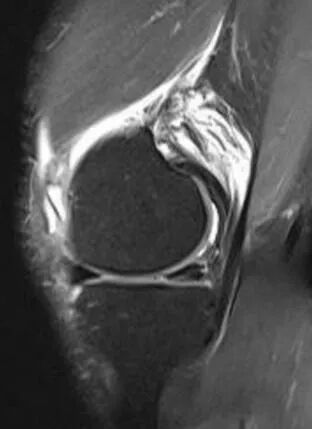

患者李先生,因外伤致左膝内侧半月板后角损伤(Ⅲ度),在腰麻下行膝关节镜下半月板缝合术,此次手术由陈功主治医师主刀,依托成熟的关节镜微创技术,在高清内镜引导下,仅通过2个微小切口便清晰显露损伤部位,运用专用缝合器械将撕裂的半月板组织精准对合、牢固固定,有效避免了传统切除手术可能带来的关节不稳、骨关节炎等远期风险。

青少年运动损伤到中老年人退行性撕裂,省荣康医院骨科团队始终以患者为中心,结合术前影像学评估与术中实时探查,为不同损伤类型、不同年龄的患者制定个性化诊疗方案。手术全程精准高效,术后搭配科室专属康复指导,帮助患者快速恢复关节活动度,多数患者术后1-3个月即可重获正常生活与运动。